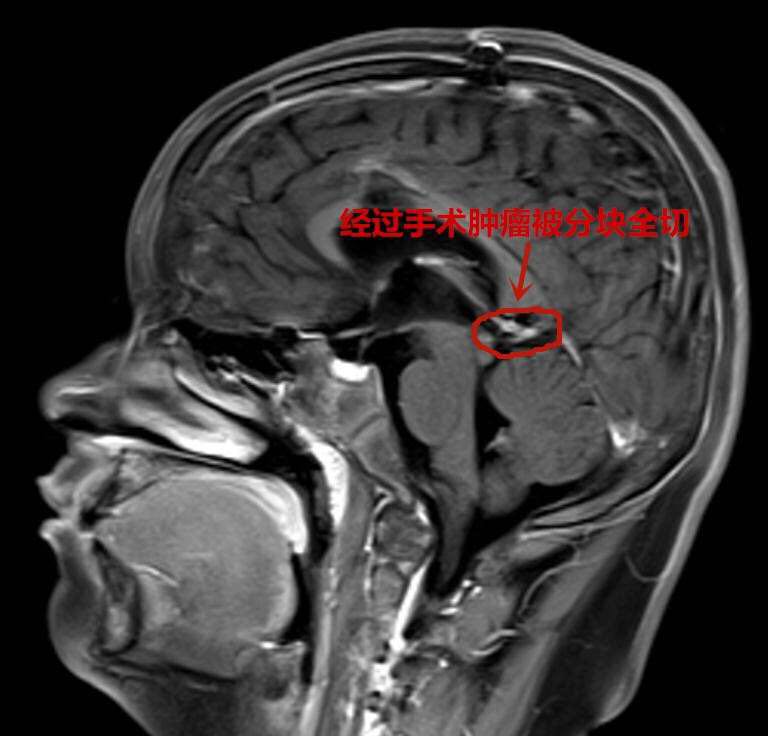

术后

为求进一步治疗,当天夜里他们便辗转到武汉脑科医院·长江航运总医院小儿神经外科。此时,军军随时都有生命危险,该科专家邵强主任连夜组织急诊手术。好在通过抢救及时保住了孩子的生命,一周后随着颅内压降低,邵强团队为军军进行了开颅手术,进行了分块全切脑瘤。邵强称,虽然患儿的肿瘤体积不大,但稍有不慎就会损伤正常脑组织和血管,引发昏迷,甚至大出血,可谓危险重重。

目前,通过病理报告证实,军军的脑瘤为先天性皮样囊肿属良性肿瘤,全切后一般不会复发。经术后恢复,他已完全恢复正常,不久即可回归校园。